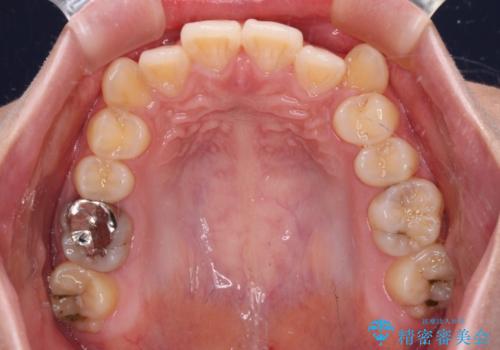

- 左右の八重歯を気にして来院された患者様です。

歯列としてはインビザラインでもワイヤー矯正でも対応できるものでしたが、インビザラインによる治療を希望されていました。

上顎の八重歯改善にインビザラインでは時間のかかってしまう可能性があり、更には口元が治療前よりも突出してしまう可能性があったため、補助装置により八重歯を事前に引き込んでおくことで、インビザラインによる治療をスムーズに行えるように計画しました。

補助装置を使用したことで、口元が突出することもなく、スムーズに仕上げることができました。